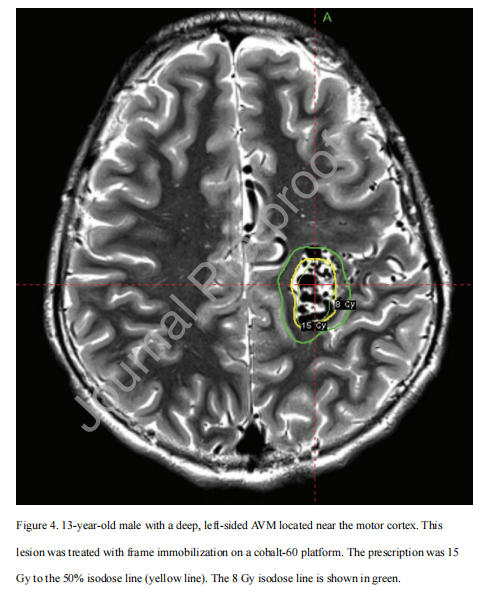

动静脉畸形(AVMs)是放射外科手术的另一个适应证,可能是先天性的或散发性的。自发性出血的风险对儿童来说尤为重要,因为儿童的自然预期寿命较长,随着时间的推移,最终出血的风险也很高(每年出血的风险高达4%,其中四分之一的出血是致命的)。放射手术,可以单次进行,也可以对较大的病变分阶段进行。可以提供一种替代侵袭性干预,如血管内栓塞或手术切除。SRS治疗是一种重要的治疗选择,有时是唯一可行的治疗选择,对于大的、深部或在明显位置的病变(图4)。体积分期SRS治疗涉及在几个月内治疗大的AVM靶区的不同部分,而剂量分期SRS治疗则以较低剂量治疗整个AVM,持续时间长达四年。然而,对于接受SRS治疗的AVM患儿来说,对整个病变的单次治疗是最常见的方法。

图4 。13岁男性,左侧深部动静脉畸形位于运动皮层附近。病变采用钴-60平台框架固定治疗。处方为15Gy,按50%等剂量线(黄线)。8Gy等剂量线用绿色表示。